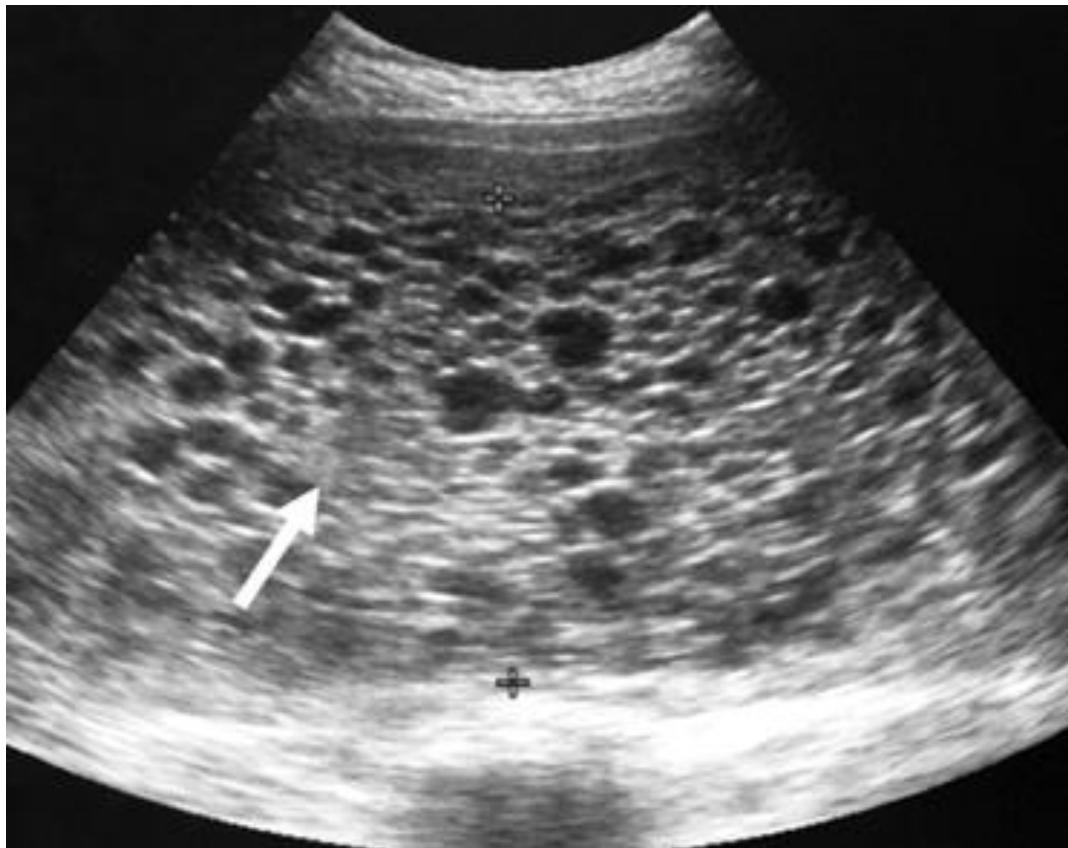

FAST / eFAST Ultrasound

- Modality: Focused Assessment with Sonography in Trauma (FAST).

- Standard 4 Views:

- RUQ (Morisonโs Pouch): Hepatorenal recess.

- LUQ: Splenorenal recess.

- Pelvic (Pouch of Douglas): Suprapubic window.

- Pericardial: Subxiphoid window.

- eFAST: Includes the pleura to check for pneumothorax/hemothorax.

- Positive Finding: Anechoic (black) fluid collection indicating blood in a trauma patient.